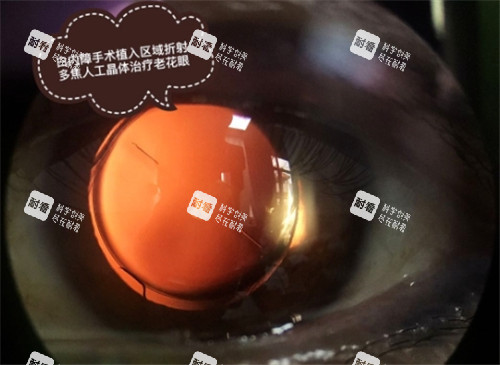

白内障是一种常见的眼科疾病,主要是由于晶状体透明度降低或者颜色改变所导致的光学质量下降的退行性改变。